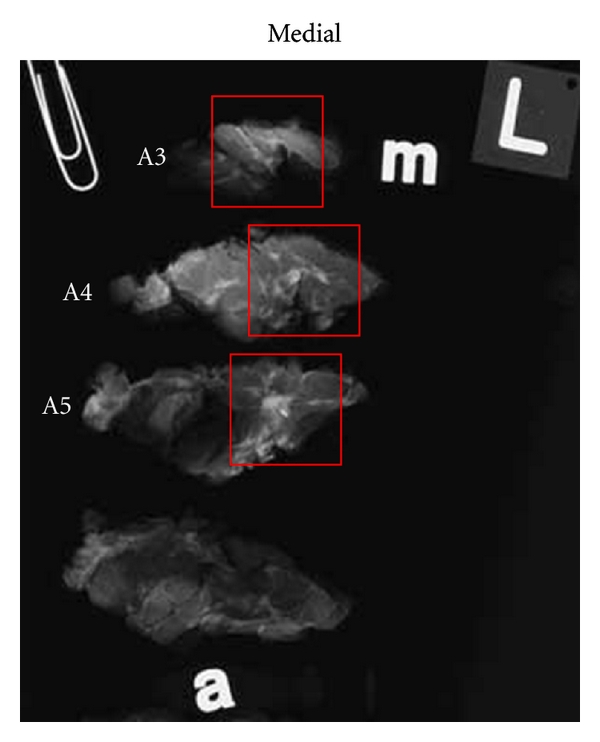

Upon receipt in the surgical pathology suite, all specimens are checked for proper surgical orientation, and any deficiencies identified are promptly corrected by the surgeon. All surgical margins are marked before sectioning with India ink with a discrete color coded to each of six axial margins. Mastectomy specimens are sectioned in the sagittal plane at uniform 5 mm increments with preservation of medial-to-lateral sequence and cephalocaudad orientation. Initially, 100% of each mastectomy specimen was submitted for specimen radiography. Experience permitted introduction of time and cost conserving measures so that approximately one-half to two-thirds of each specimen was submitted for radiography, focusing on the location of previous biopsy or lumpectomy sites and any additional guidance provided by breast surgeons and imagers. Breast-conserving specimens and reexcisions are inked for margins and sectioned at 5 mm increments. The plane of sectioning varies with the requirements of the case. Occasionally, demonstration of maximum extent of disease or multifocality in one plane is of paramount importance. In these cases, the plane of sectioning is guided by image interpretation of size, extent, and multifocality, and sections are typically made in the coronal (frontal) plane. In cases where the status of chest wall or anterior cutaneous margins (or both) are of particular concern or the sagittal plane shows maximum extent, the sagittal plane is selected for sectioning and large-format section submission. This approach allows convenient correlation of sagittal large histology sections with MRI sagittal-reconstructed images. All BCS and reexcision specimens are entirely submitted for specimen radiography.

Orientation of all specimens is maintained with the use of radioopaque alphabet characters to denote axis margins in each plane as well as the sequence of sections, for example, “superficial to deep” in the coronal plane or “medial to lateral” in the sagittal plane. Tissue slices are placed on previously exposed radiographic film with orienting characters and transported expeditiously to the breast imaging facility for radiography. Following specimen radiography and radiographic interpretation (vide infra), the specimen with accompanying radiographs is returned for pathologic examination with a “Large-Format Specimen Checklist” detailing the clinical and specimen radiographic findings in written narrative and using template diagrams of both breasts. This worksheet communicates the clinical and radiographic findings of concern with specific questions to be addressed pathologically. Imaging abnormalities visible mammographically are marked directly on the films with a wax pencil as a guide for histopathologic section submission (Figure 1). The location and extent of ultrasound or MRI-detected findings, not visible mammographically or with specimen radiography, are marked on the specimen radiographs. Section(s) best demonstrating critical findings such as proximity to margins or maximum extent of neoplasm are encircled for possible large-format submission.

Following traditional pathologic specimen examination with gross inspection and palpation, sections are selected for histologic study to incorporate gross pathologic findings as well as findings of concern communicated by imagers and surgeons (Figure 2). Microscopic evaluation of surgical margins is typically accomplished with a combination of both large-format and conventionally sized tissue blocks. Large sections usually permit margin evaluation along 100% of the circumference of a BCS specimen and are selected to encompass critical margins whenever close proximity to a surgical line of excision is suspected. Margins perpendicular to the large-format plane of section are usually submitted as conventional tissue blocks. Orientation of all conventionally sized margin sections is perpendicular to the specimen surface to allow measurement of margin width to the nearest whole millimeter. The precise location of these perpendicular margins is selected with guidance from both imaging and clinical information and conventional pathologic examination. Reexcision specimens, including surgical shave excisions of biopsy cavities, are sectioned and oriented perpendicular to the surgical margin so that margin distance from the cavity to the new surgical margins remains measureable. The anatomic location of all tissue blocks removed from the specimen is recorded in the gross dictation narrative of the pathology report as well as on the specimen radiographs which are preserved as a permanent record of pathology slide origin. This record is provided to the pathologist at microscopic sign-out as an aid in the reconstruction of the specimen in three dimensions.

2.4. Breast Imaging Department Specimen Radiography Protocol

Upon receipt in the imaging center, specimens are placed in an analog specimen radiography unit (Faxitron Bioptics, LLC). Specimen film images are examined by a breast imager, and all relevant mammograms, core biopsy specimen radiographs, wire-localization images, ultrasound, and MRI studies are reviewed. Mammographically detected lesions of concern are marked on the radiograph films, and the location of mammogram occult abnormalities identified with ultrasonography and MRI is encircled. To facilitate communication of clinical, presurgical imaging and specimen radiography findings to the pathologist, the “Large-format Specimen Checklist” is completed with reference to notations made by the imager on the specimen radiographs. A graphical depiction of the location and extent of clinical and imaging-suspected neoplasia is marked on a template bilateral breast diagram. A written narrative conveys clinical concerns and imager-initiated questions for pathologist reconciliation. This form is returned with the specimen and annotated specimen radiographs to the surgical pathology suite.